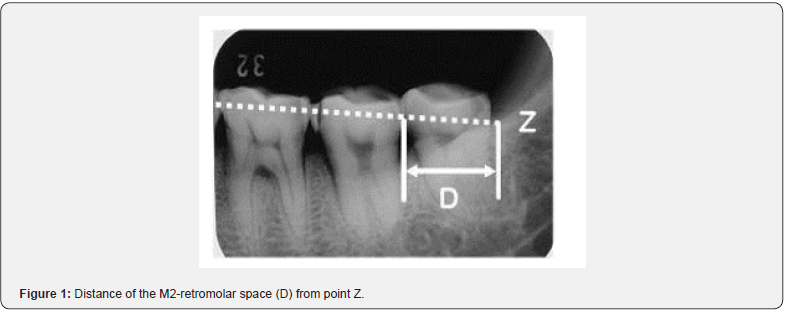

In examining the alignment status of the third molars, the horizontal position observed on the radiographs was defined as the case where the tooth axis was almost parallel to the occlusal plane, the inclined position was defined as the case where the third molars encroached on the distal cervical portion of the second molars and/or the tooth axis was inclined at approximately 45 degrees to the occlusal plane, and the upright position was defined as the case where the tooth axis was almost perpendicular to the occlusal plane. Congenital absence was defined as the absence of tooth embryos in the alveolar bone on radiographs and no history of tooth extraction in the past. Both the inclined and horizontal positions were difficult to erupt with ease, and both were combined as eruption difficulty (inclined + horizontal). On the molar radiographs, the intersection point (Z) was defined as the point of intersection between the extension of the straight line connecting the most mesially protruding point of the first molar and the most distally protruding point of the second molar and the internal oblique line. This point (Z) was used as a reference for the end point of the retromolar space. The distance (D= M2-retromolar space) from the distal surface of the mandibular second molar to the Z point (Figure 1) was measured and compared with the mesiodistal diameter of the mandibular second molar [12]. First, 30 individuals in each category were examined according to the following criteria. The frequency of this category was calculated as 〇 if the distance (D) was greater than the mesiodistal diameter of the second molar, △ if it was within half of this distance from the mesiodistal diameter of the second molar, and ✕ if it was less than half, and then the relationship between the frequency of this category and eruptive status was compared.

Measuring the retromolar space is difficult even in excavated skulls and even more impossible in vivo. To determine the size of the retromolar space in the present study, a “Z” point was developed on the radiographs [12]. This point is slightly different from the Xi point (near the mandibular foramen) used in orthodontics [19]. In addition, an attempt was made to compare the relative size of the M2-retromolar space with the size of the second molar over time.

The relationship between eruption status and M2-retromolar clearance showed that as the eruption style of mandibular third molars changed from upright→inclined→horizontal, the size of the M2-retromolar space gradually decreased. In congenital absence, most of the M2-retromolar gap was less than 1/2 of the mesiodistal diameter of the second molar (Table 1). In modern populations, the eruption alignment of the mandibular third molars was largely dependent on the size of the M2-retromolar clearance. Similar results were obtained in a quantitative analysis of the M2-retromolar space [12].